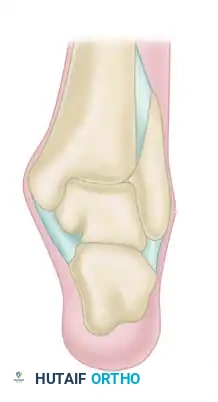

Scranton and McDermott developed a widely utilized radiographic classification system for anterior ankle spurs, which correlates directly with the degree of joint involvement, treatment complexity, and prognostic recovery:

Grade I (Synovial Impingement): Radiographs demonstrate an inflammatory reaction with minor tibial spurs measuring up to 3 mm.

Grade II (Osteochondral Reaction Exostosis): Radiographs show tibial spurs larger than 3 mm. No corresponding talar spur is present.